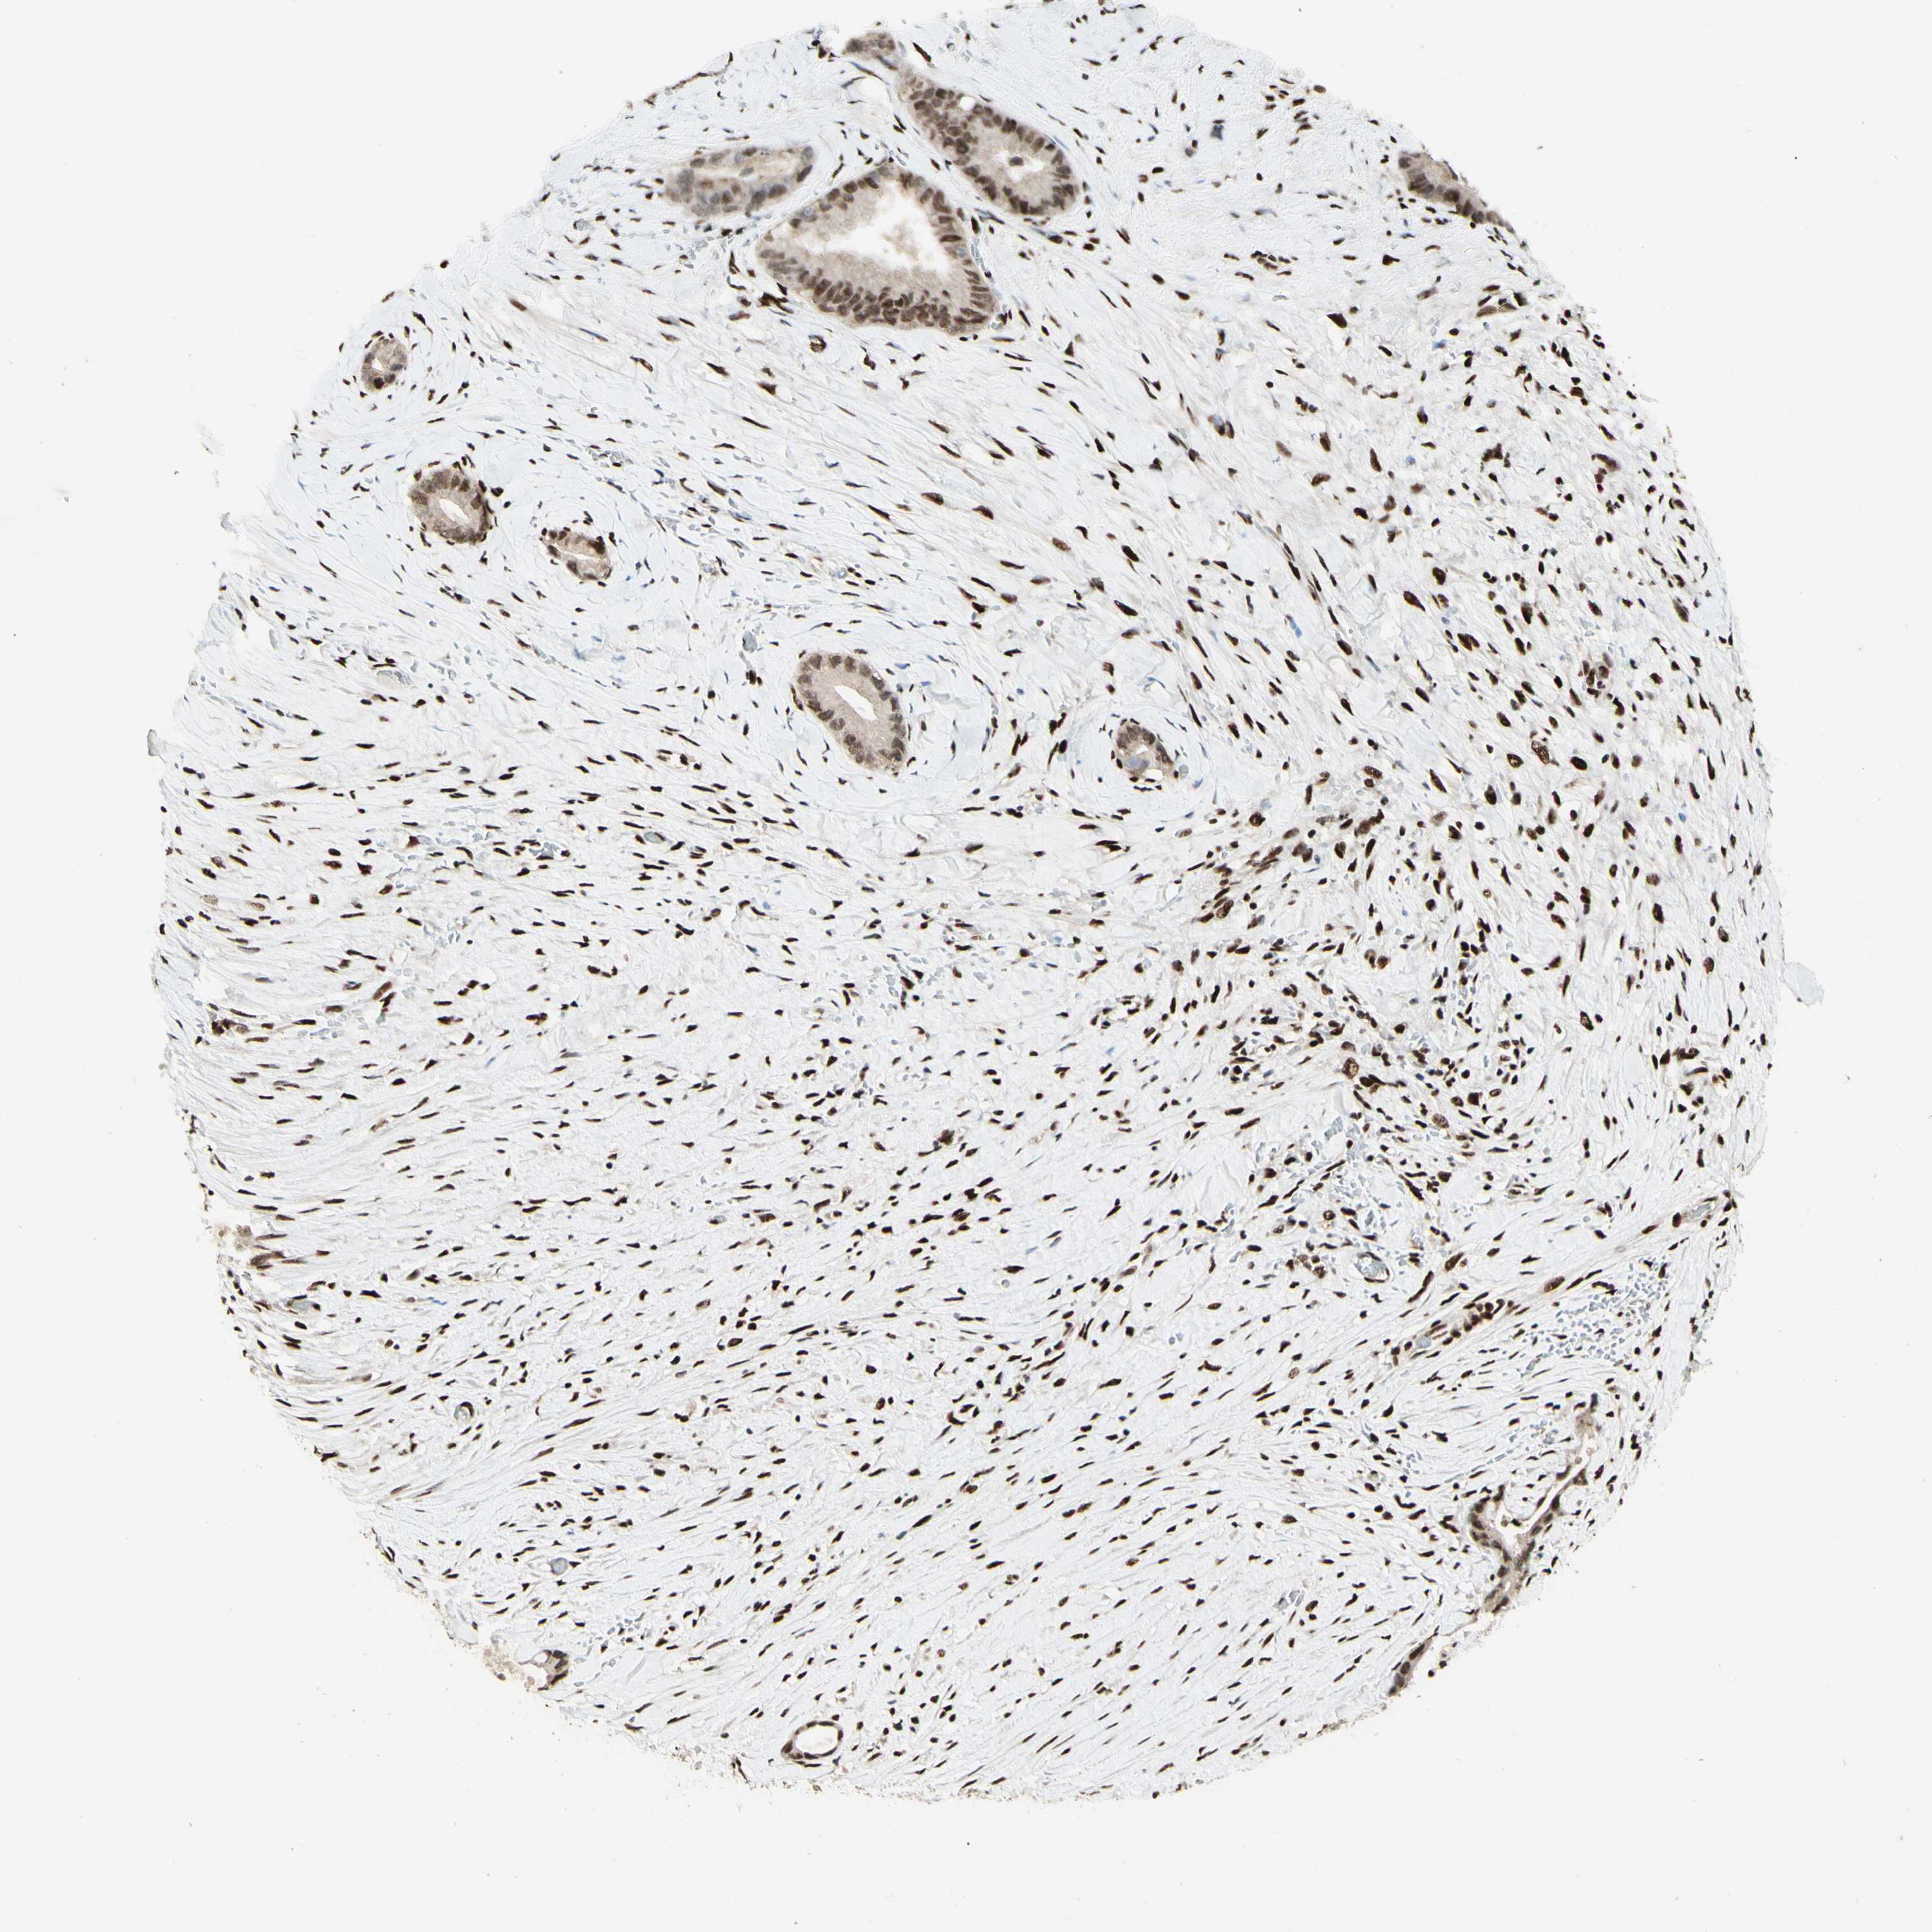

LIVER CANCER - Protein expressioni

A mouse-over function shows sample information and annotation data. Click on an image to view it in a full screen mode. Samples can be filtered based on level of antibody staining by selecting one or several of the following categories: high, medium, low and not detected. The assay and annotation is described here.

Note that samples used for immunohistochemistry by the Human Protein Atlas do not correspond to samples in the TCGA dataset.

Antibody stainingi

Antibody staining in the annotated cell types in the current human tissue is reported as not detected, low, medium, or high, based on conventional immunohistochemistry profiling in selected tissues. This score is based on the combination of the staining intensity and fraction of stained cells.

Each image is clickable and will lead to virtual microscopy that enables deeper exploration of all samples and also displays staining intensity scores, fraction scores and subcellular localization as well as patient and tissue information for each sample.

Antibody HPA004248

Antibody CAB010435

Staining

High

Medium

Low

Not detected

Intensity

Strong

Moderate

Weak

Negative

Quantity

>75%

75%-25%

<25%

None

Location

Nuclear

Cytoplasmic/membranous

Cytoplasmic/membranous,nuclear

Cholangiocarcinoma

Carcinoma, Hepatocellular, NOS